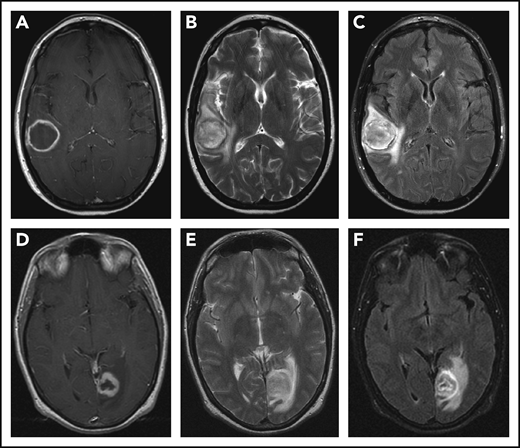

CNS imaging findings in LYG. T1-weighted postcontrast (A,D), T2-weighted (B,E), and fluid attenuation inversion recovery (C,F) sequences from MRI of the brain in a 43-year-old woman (A-C) with LYG demonstrates a large, enhancing right temporal lesion with central necrosis, and in a 39-year-old man (D-F) with LYG demonstrates a large, enhancing left posterior occipital lesion with central necrosis.

CNS involvement is seen in approximately one-third of LYG cases and demonstrates a variable spectrum of clinical symptoms and imaging findings.12,13,17,19 Neurologic symptoms depend on the site of CNS involvement and may include hearing loss, diplopia, dysarthria, hemiparesis, ataxia, and atonic bladder, and many but not all patients with abnormal radiographic findings on brain magnetic resonance imaging (MRI) have clinical symptoms.17 Focal intraparenchymal lesions are most common on MRI and are characterized by multiple foci of abnormal increased signal intensity on fluid attenuation inversion recovery and T2-weighted imaging (Figure 3).17 Abnormal punctate or linear foci of enhancement are frequently observed in these lesions, with enhancing lesions typically residing along medullary vessels, reflective of the angiocentricity of disease. Enhancing lesions can also evolve over time with up to one-third of heterogeneously enhancing intracranial masses evolving into a ringlike enhancing lesion with a nonenhancing center (Figure 3A,D).17 Abnormal enhancement of the cranial nerves and/or leptomeninges is also seen in LYG and can lead to cranial nerve palsy of the affected nerves.17 Less common imaging findings include enhancement and engorgement of the choroid plexus and/or thickening of the dura mater.